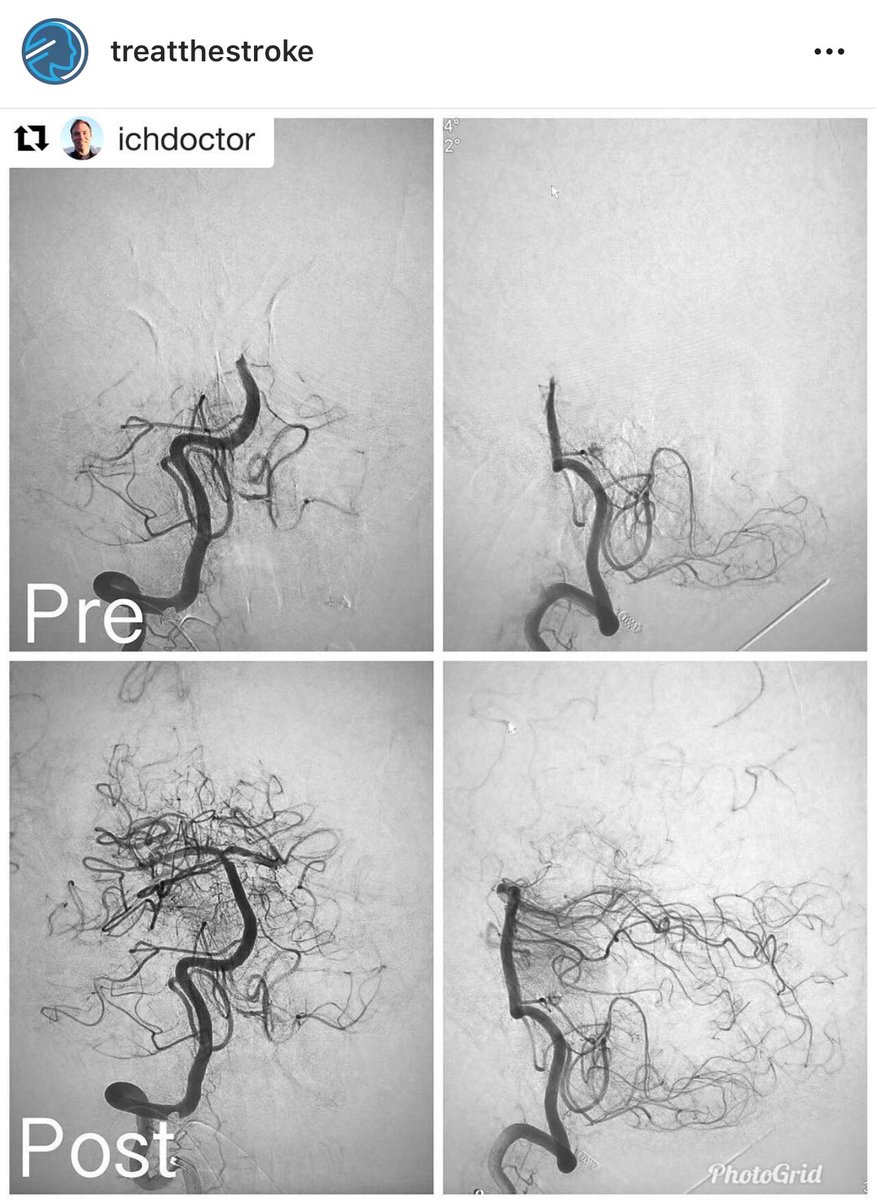

#ThrombectomyThursday - #Repost from our colleague Dr. Christopher Kellner · NYC Neurosurgeon Mount Sinai Neurosurgery, aspiration thrombectomy of a distal basilar occlusion with a single-pass via right transradial approach to avoid the dissection. TICI 2B (persistent left SCA occlusion). instagram.com/p/BnrYeSEhdfd/…

#ThrombectomyThursday - #Repost from our colleague <a href="/chriskellnerMD/">Dr. Christopher Kellner · NYC Neurosurgeon</a> <a href="/MountSinaiNeuro/">Mount Sinai Neurosurgery</a>, aspiration thrombectomy of a distal basilar occlusion with a single-pass via right transradial approach to avoid the dissection. TICI 2B (persistent left SCA occlusion). instagram.com/p/BnrYeSEhdfd/…